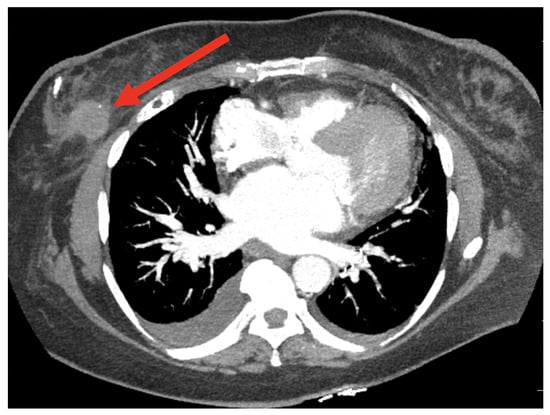

8.4. Breast Cancer Detection Using Computed Tomography (CT) Scan Images

8.4.1. Model Performance on CT Image: Pros, Cons, and Future Directions

- Desperito, E.; Schwartz, L.; Capaccione, K.M.; Collins, B.T.; Jamabawalikar, S.; Peng, B.; Patrizio, R.; Salvatore, M.M. Chest CT for breast cancer diagnosis. Life 2022, 12, 1699. [Google Scholar] [CrossRef]